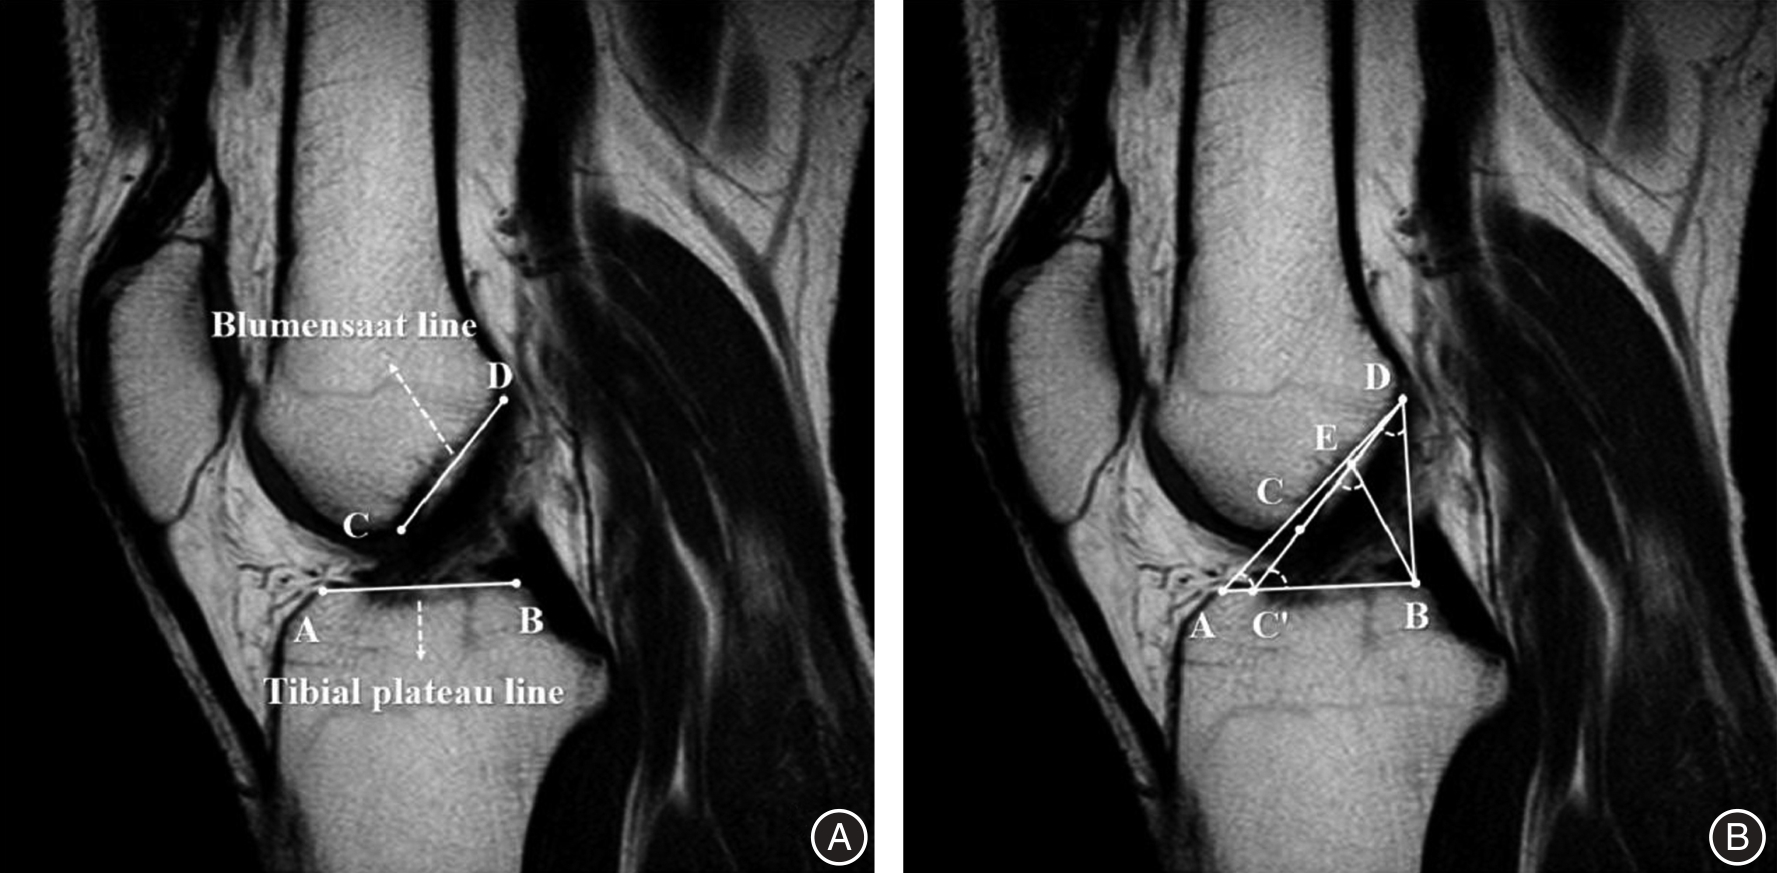

Objective To investigate whether the geometric triangular relationship between the Blumensaat line and the tibial plateau can serve as an auxiliary diagnostic index for identifying and evaluating anterior cruciate ligament (ACL) injuries, thereby enhancing diagnostic accuracy. Methods A retrospective self?controlled study was conducted involving 64 patients diagnosed with unilateral ACL injury via arthroscopy and treated with ACL reconstruction at Qingdao Municipal Hospital from January to August 2023. Ultimately, 40 cases were included in the analysis. Preoperative MRI images of the affected knees and contralateral healthy knees were collected as the ACL injury group and control group, respectively. In the MRI images, point C, point D, and point E were defined as the anterior end, posterior end, and midpoint of the Blumensaat line, respectively; point A and point B were defined as the turning points of the anterior and posterior edges of the tibial plateau, respectively; and point C' was defined as the intersection of the extension line of DC and line AB. Based on these anatomical landmarks, angles ∠DAB, ∠CEB, ∠DC'B, and ∠CDB were established. The intra?class correlation coefficient (ICC) was calculated to assess measurement consistency and reproducibility. Differences between the aforementioned angles were compared, and the area under the receiver operating characteristic (ROC) curve was computed to evaluate diagnostic performance. Results For ∠CDB, ∠DC'B, ∠CEB, and ∠DAB, the intra?group and inter?group correlation coefficients all exceeded 0.80, indicating excellent consistency and reproducibility. Compared to the control group, the angles ∠CDB, ∠CEB, and ∠DAB in the ACL injury group were significantly reduced (P < 0.001). Among these, ∠DAB appears to be the most reliable index for diagnosing and evaluating ACL injuries, with an area under the receiver operating characteristic curve (AUC) of 0.829, a cut?off value of 42.2°, a sensitivity of 82.5%, and a specificity of 80.0%. Conclusion The geometric triangular relationship between the Blumensaat line and the tibial plateau in MRI images, particularly the angle ∠DAB, can serve as an auxiliary indicator for diagnosing and evaluating ACL injuries, thereby enhancing diagnostic accuracy.